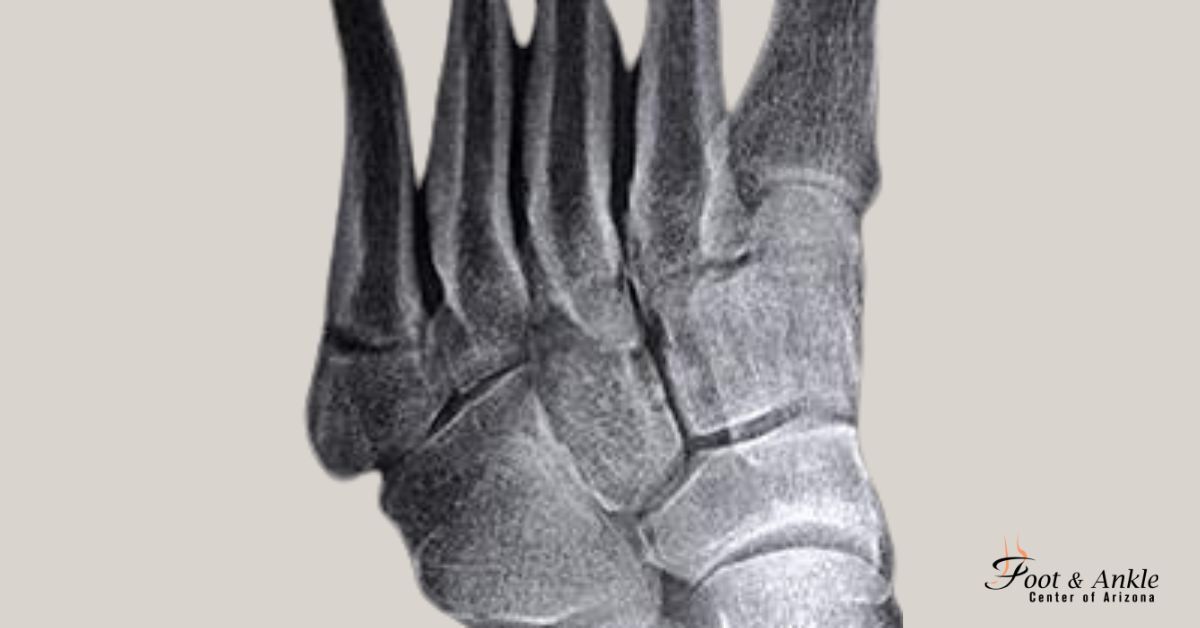

- How is a base of 5th metatarsal fracture diagnosed?

Diagnosis is made through bodily exam and imaging assessments which includes X-rays or MRI scans to decide the extent of the fracture.